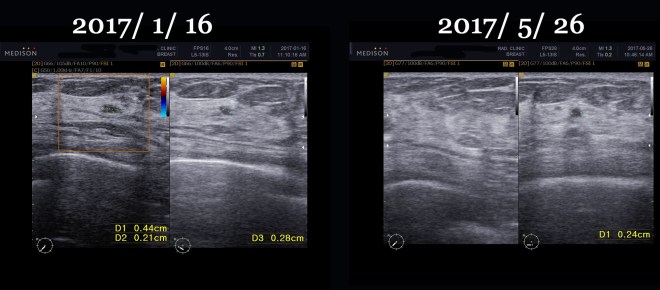

• 2017년 1월 16일 종양 완전소실  4.4×2.1mm의 흔적남음

• 2017년 5월 26일 초음파상 종양완전소실  2.4mm의 양성으로 보이는 흔적남음

이 환자는 1년간 내 치료를 잘 따라 주었고 마음이 안정이 되어서 현재 사회생활도 하고 있다. 5월중에 초음파를 다시 비교하였다. 2017년 1월달에 추적검사를 하였고 다시금 5개월 뒤에 추적검사를 하였다.

1. 2017년 1월 16일 초음파 추적검사

2017년 5월 26일 초음파 추적검사

그래서 초기 자료와 비교를 해 보면 다음과 같다.

이후한방치료와 tamoxifen 요법을 병행하면서 위의 결과와 같이 양성의 흔적만 보인다.